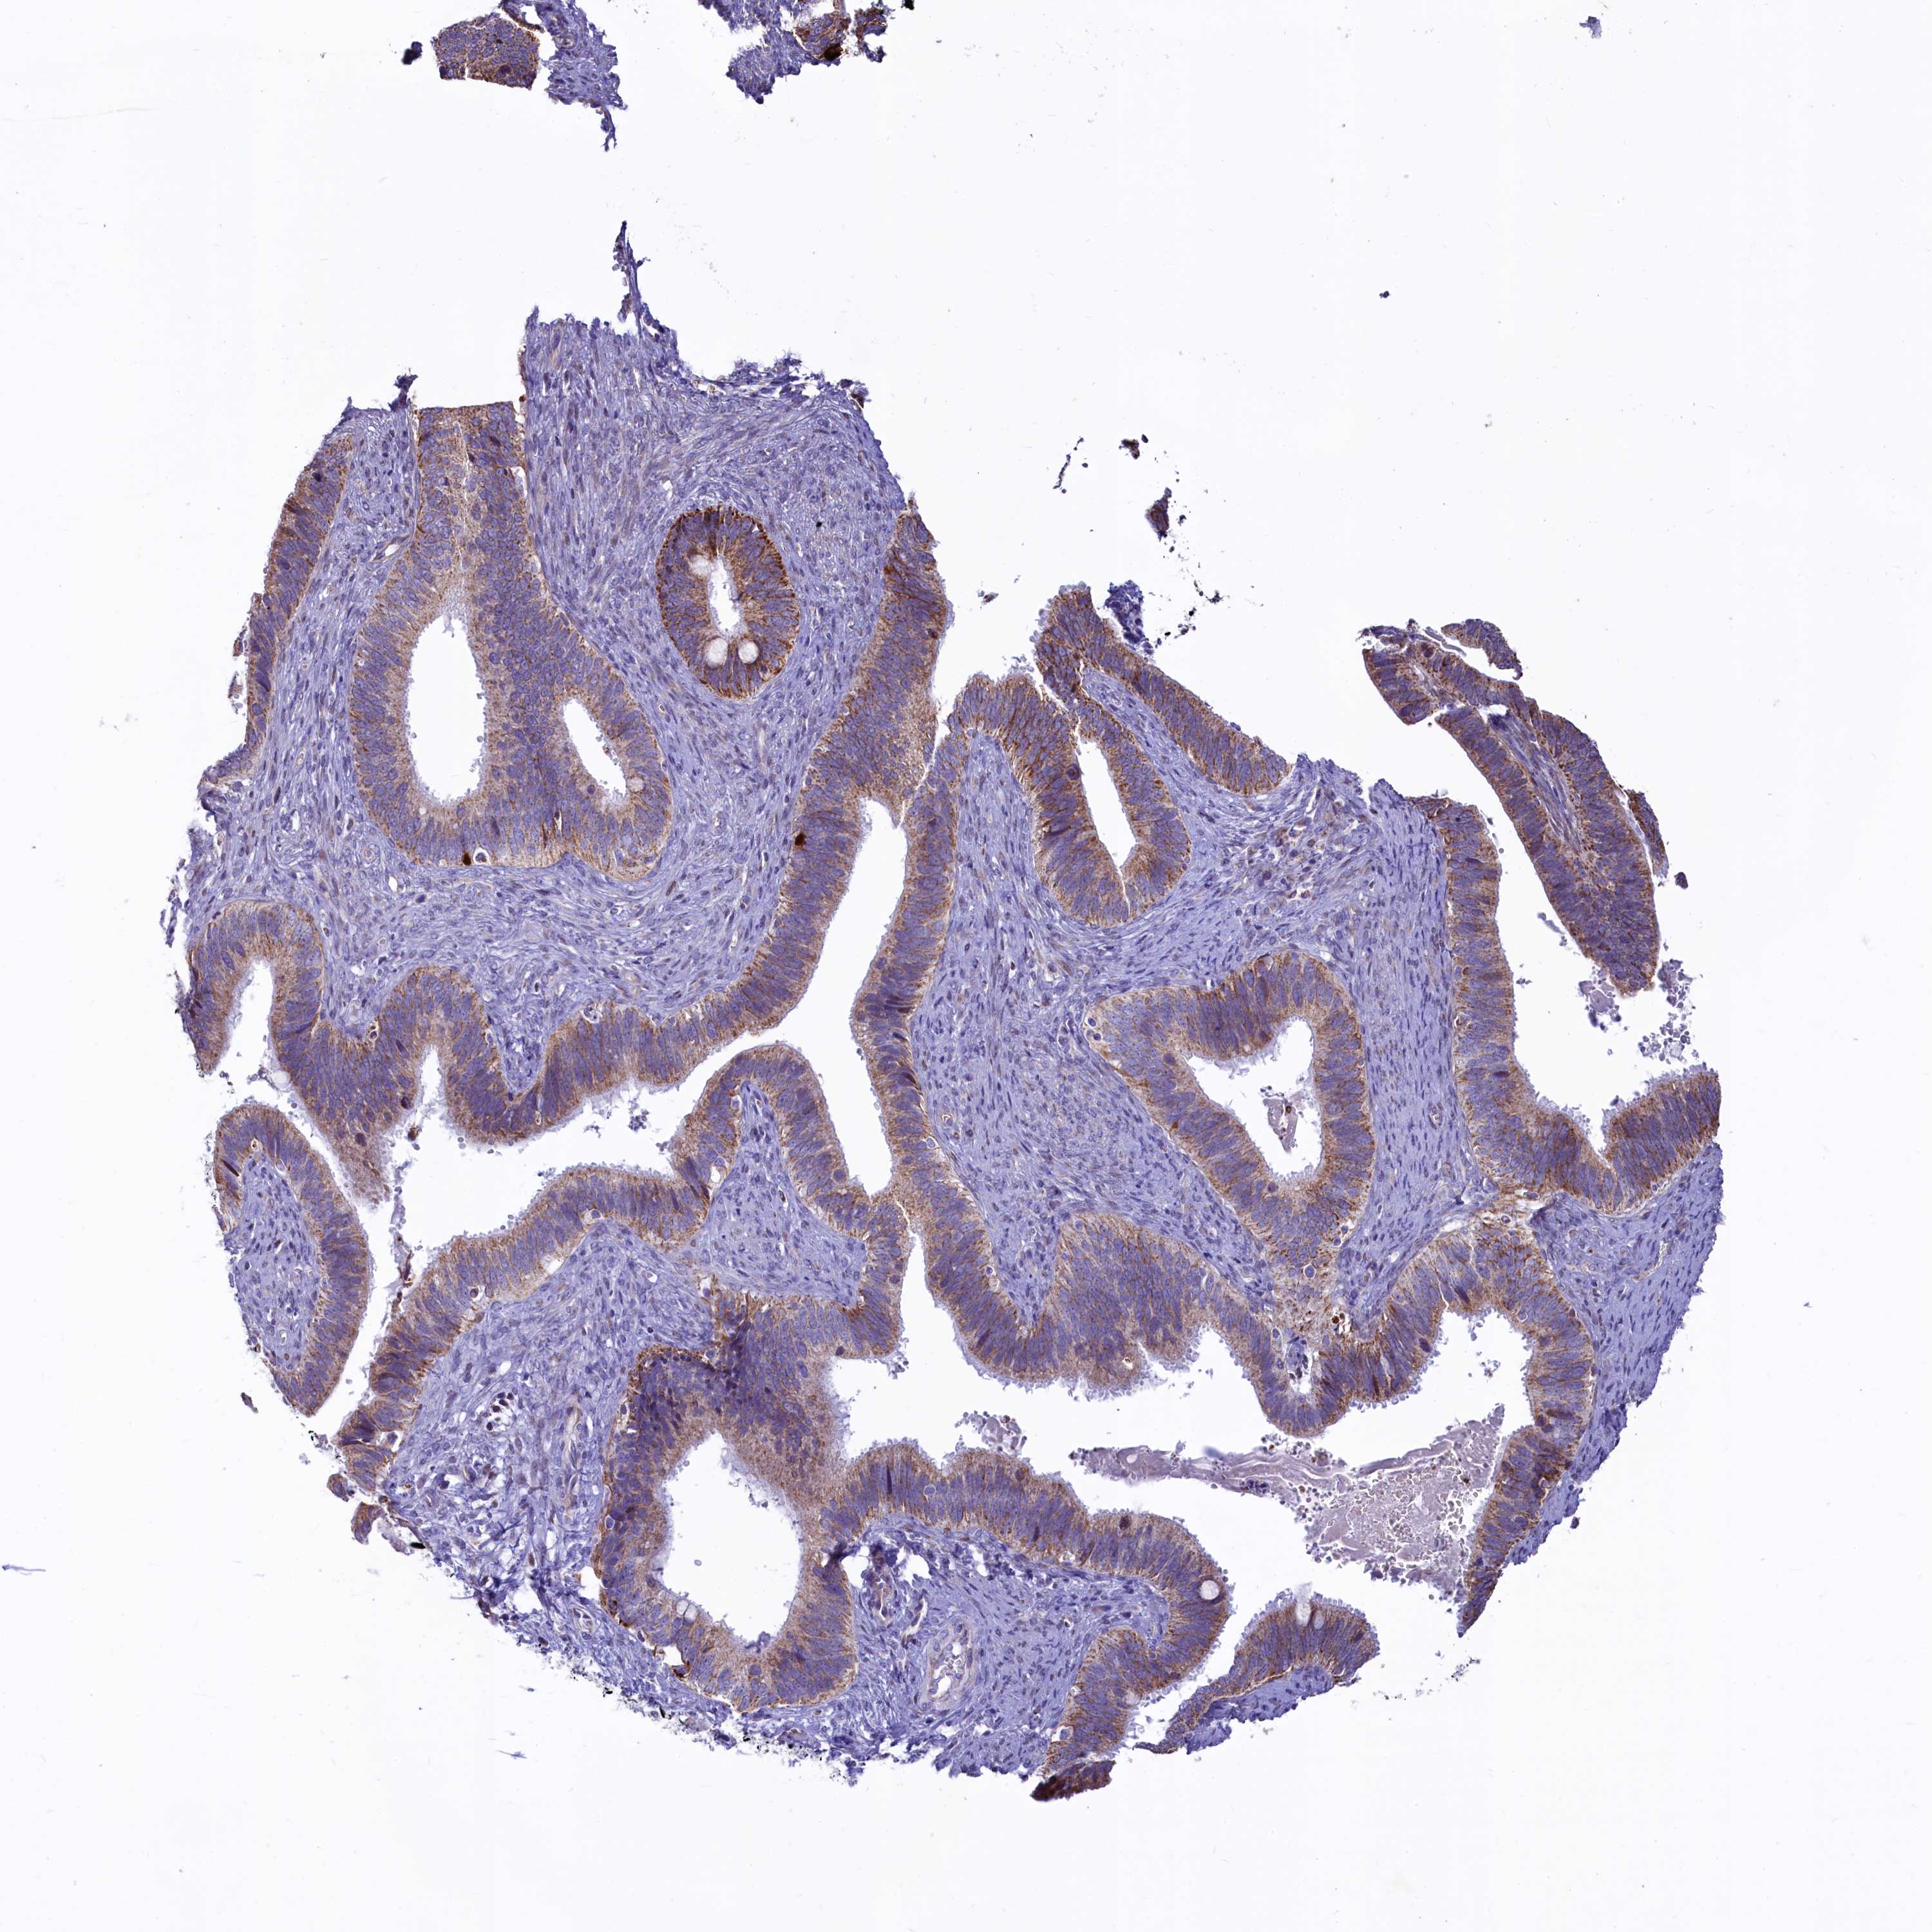

CERVICAL CANCER - Protein expressioni

A mouse-over function shows sample information and annotation data. Click on an image to view it in a full screen mode. Samples can be filtered based on level of antibody staining by selecting one or several of the following categories: high, medium, low and not detected. The assay and annotation is described here.

Note that samples used for immunohistochemistry by the Human Protein Atlas do not correspond to samples in the TCGA dataset.

Antibody stainingi

Antibody staining in the annotated cell types in the current human tissue is reported as not detected, low, medium, or high, based on conventional immunohistochemistry profiling in selected tissues. This score is based on the combination of the staining intensity and fraction of stained cells.

Each image is clickable and will lead to virtual microscopy that enables deeper exploration of all samples and also displays staining intensity scores, fraction scores and subcellular localization as well as patient and tissue information for each sample.

Antibody HPA040401

Antibody HPA043921

Staining

High

Medium

Low

Not detected

Intensity

Strong

Moderate

Weak

Negative

Quantity

>75%

75%-25%

<25%

None

Location

Nuclear

Cytoplasmic/membranous

Cytoplasmic/membranous,nuclear

Squamous cell carcinoma, NOS

Adenocarcinoma, NOS